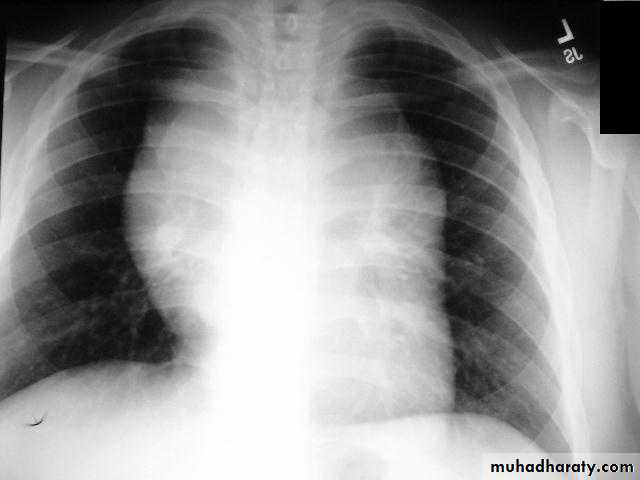

Pericardial effusions occur when fluid collects in the pericardial space (a normal pericardial sac contains approximately 30-50 mL of fluid).

adiographic features

Plain radiograph

a very small pericardial effusion can be occult on plain film

there can be globular enlargement of the cardiac shadow giving a water bottle configuration known as Globe shape heart or pumpkin shape heart .

Pericardial effusion